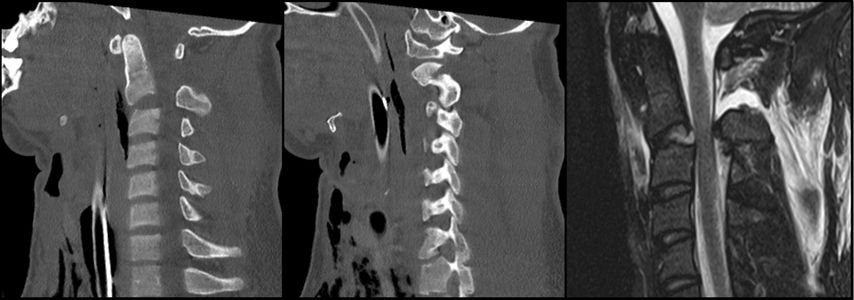

Abb. 2: CT, MRT und Versorgungsstrategie bei einer stark dislozierten Densfraktur Typ IIb mit begleitender Atlasbogenfraktur bei einer geriatrischen Patientin

Etwa 20% aller Wirbelkörperfrakturen im zervikalen Bereich sind Densfrakturen, die typischerweise eine bimodale Altersverteilung aufweisen: Ein kleiner Teil betrifft jüngere, sportlich aktive Männer – die Mehrheit der Betroffenen sind jedoch Frauen über 65 Jahre, welche auf Bodenniveau stürzen.10 Die Mortalität dieser Verletzungen kann mit jener von Schenkelhalsfrakturen im geriatrischen Kollektiv verglichen werden und beträgt rund 14% nach 30 Tagen sowie 44% nach zwei Jahren.11 Eine bestehende Arthrose des atlantoaxialen Gelenks, degenerative subchondrale zystische Veränderungen des Dens sowie eine verminderte Beweglichkeit der subaxialen Wirbelsäule bei geriatrischen Patient:innen erhöhen die mechanische Belastung auf die oberen Segmente der Halswirbelsäule.12 Dies begünstigt an der biomechanischen Schwachstelle – der Densbasis – das Auftreten einer Fraktur.10 Die Klassifikation nach Anderson und D’Alonzo, modifiziert durch Grauer, hat sich aufgrund ihrer prognostischen und therapeutischen Relevanz als Standard für die Einteilung der Densfrakturen etabliert.13,14 Typ I ist eine Abrissfraktur der Ligamenta alaria an der Densspitze, gilt als stabil und wird in der Regel konservativ behandelt. Typ II betrifft den Übergangsbereich des Dens zum Corpus und ist mit Abstand die häufigste Densfraktur, welche als potenziell instabil gilt. Grauer unterscheidet innerhalb der Typ-II-Frakturen die Subtypen IIa (transversaler Frakturverlauf), IIb (Frakturverlauf von anterosuperior nach posteroinferior) und IIc (von anteroinferior nach posterosuperior). Typ III sind Frakturen des Corpus der Axis, welche in der Regel konservativ behandelt werden können. Die Behandlung der Typ-II-Densfraktur bei älteren Patient:innen wird nach wie vor kontrovers diskutiert. Während einige Studien eine operative Versorgung zur Verbesserung der Fusionsrate sowie der Lebensqualität empfehlen, weisen andere darauf hin, dass auch eine konservative Therapie bei geriatrischen Patient:innen ein zufriedenstellendes funktionelles Ergebnis und eine geringe Komplikationsrate ermöglichen kann.11 Die Operationsindikation ergibt sich bei nachgewiesener Instabilität oder bei neurologischer Verschlechterung, etwa infolge einer Myelopathie. Zu berücksichtigen ist, dass bei konservativer Behandlung das Risiko einer Pseudarthrose mit daraus resultierenden chronischen Beschwerden sowie einer möglichen progredienten neurologischen Verschlechterung besonders bei aktiven älteren Patient:innen erhöht ist. Die Blutversorgung des Dens erfolgt überwiegend durch ein Gefäßnetz aus aufsteigenden Ästen der A. vertebralis, das an der Spitze des Dens eine Anastomose und an der Basis einen Gefäßplexus bildet. Diese Gefäßversorgung wird bei Typ-II-Frakturen häufig unterbrochen, was die Knochenheilung negativ beeinflusst.15 Für die Beurteilung der Instabilität gelten folgende Kriterien: eine Dislokation von mehr als 5mm, ein Frakturspalt von über 2mm oder ein kyphotischer Winkel von mehr als 11°.10 Frische IIa- und IIb-Densfrakturen eignen sich für eine ventrale Schraubenosteosynthese. Die dorsale Fusion wird hingegen für IIc-Frakturen, Trümmerbrüche des Dens, stark dislozierte Frakturen sowie bei bereits bestehender Pseudoarthrose bevorzugt.15 Der Halo-Fixateur wird bei geriatrischen Patient:innen heute nicht mehr empfohlen,5,10,11,15 da die Komplikationsrate mit über 30% sehr hoch ist. Häufige Komplikationen umfassen Aspirationspneumonien, Infektionen der Pin-Stellen sowie Druckstellen, Schluckbeschwerden und eine insgesamt erhöhte Mortalität.